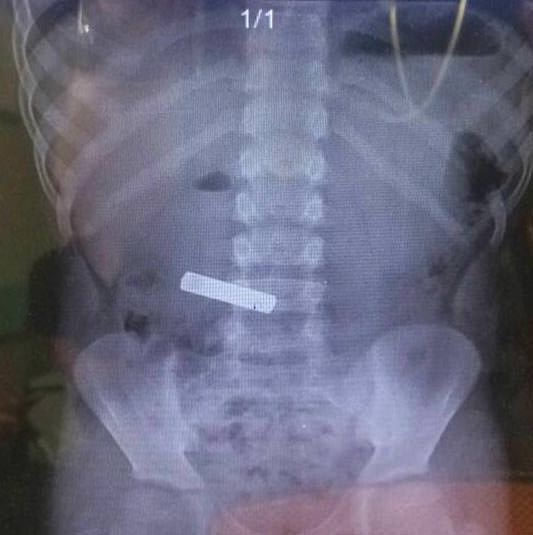

İzmir'deki Tepecik Eğitim ve Araştırma Hastanesi Çocuk Gastroenteroloji Bölümü'nün, yabancı cisim yutan çocukların nefes ve borusu ile midelerinden çıkarttığı, anahtarlık, madeni para, saat pili, ataç, çengelli iğne ve çivi gibi objeler görenleri şaşkına çevirdi.

"Çocukların nefes ve borusu ile midelerinden çıkartılan, anahtarlık, madeni para, saat pili, ataç, çengelli iğne ve çivi gibi objeler görenleri şaşkına çevirdi. "